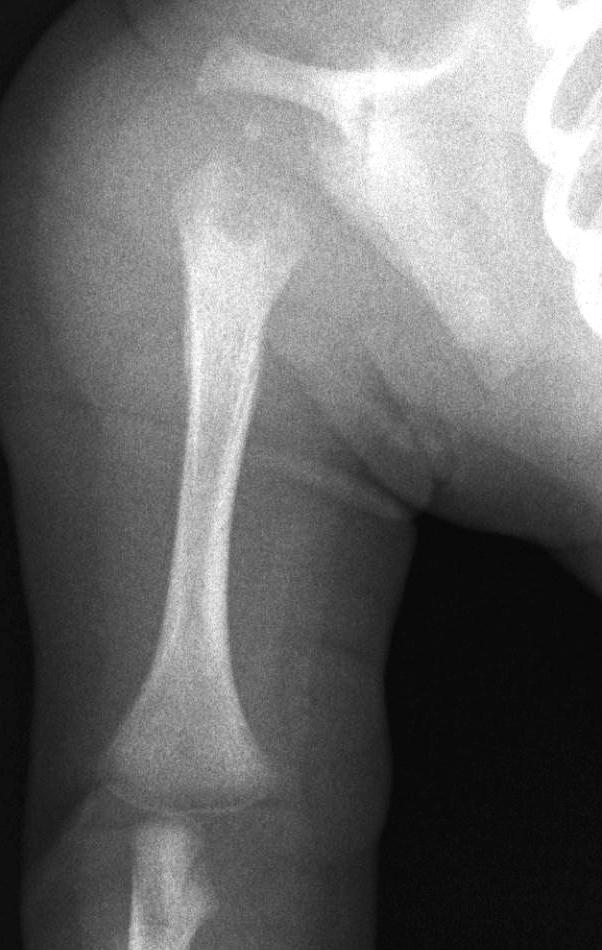

Image

37.a.

37.b.

37.c.

37.d.

37. a-d) X-ray of the right humerus. a. Rarefaction in the proximal-medial part of metaphysis of the right humerus – early osteomyelitis. b. Two weeks after the lytic area has grown. c. 1 month later sclerotic regeneration has begun. d. 4 months after almost complete healing. Osteomyelitis, infant.